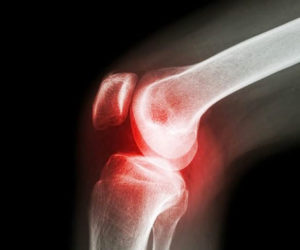

Каждая стадия имеет свои типичные рентгенологические признаки. Это важно для постановки диагноза и назначения лечения.

На снимке можно заметить сужение щели между суставными поверхностями, разрастание остеофитов и истощение костной ткани. В зависимости от стадии. варьируется степень выраженности данных признаков.